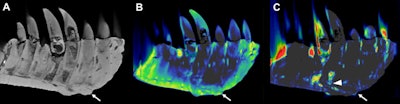

CT reconstructions of the tooth-bearing part of the left dentary. (A) Reconstruction of the conventional CT images in lateral view showing well-preserved anatomical structures, such as the replacement teeth. The arrow indicates the focal exophytic mass -- the abnormal growth that sticks out from the surface of the tissue -- on the ventral surface at the level of the third to fifth tooth roots. (B) The DECT-based calcium material map shows a homogeneous mineral distribution, while (C) the fluorine material map shows significant mineral accumulation in the center of the exophytic mass and adjacent tooth roots (arrowhead). All images courtesy of Hamm et al.To overcome the challenges of the fossil's high density, the researchers manipulated the CT scanner's current and voltage to minimize artifacts and improve image quality.

The left dentary of the jaw showed a diffuse thickening of nearly the entire dentary and a mass on its surface that extended to the root of one of the teeth. Inside the mass, DECT detected a significant accumulation of the element fluorine, which is associated with decreased bone density. The mass and fluorine accumulation findings supported a diagnosis of tumefactive osteomyelitis, an infection of the bone.